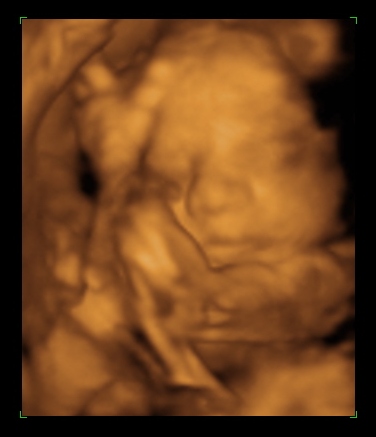

Rólunk: tegnap voltam a dokinál, nagy valószinüséggel kislány a Pötty babánk (de még nem mondta tutira a doki, mert eléggé összezárta a lábikóit)